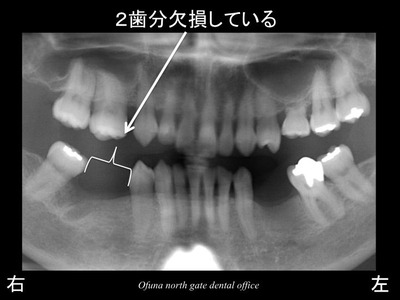

この欠損部は、2歯分の欠損があります。

しかし、欠損部は2歯欠損のスペースはありません。

1歯と半分程度の隙間です。